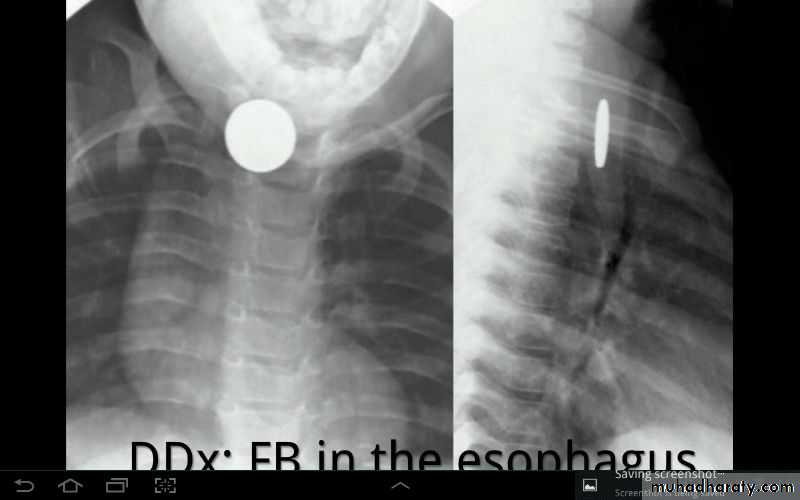

Foreign body in esophagus

Foreign body in right esophagus